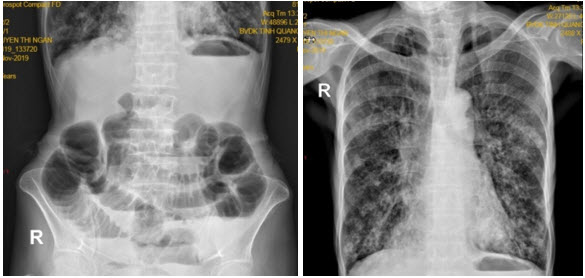

Bệnh nhân được chụp Xquang bụng: các quai ruột non giãn lớn kèm mức hơi dịch. Xquang phổi : hình ảnh dày thành kèm giãn phế quản dạng tổ ong (chụp nằm) (Hình 2). Siêu âm ổ bụng thấy hình ảnh giãn kèm tăng nhu động một số quai ruột non.

Hình 2. Xquang bụng và ngực